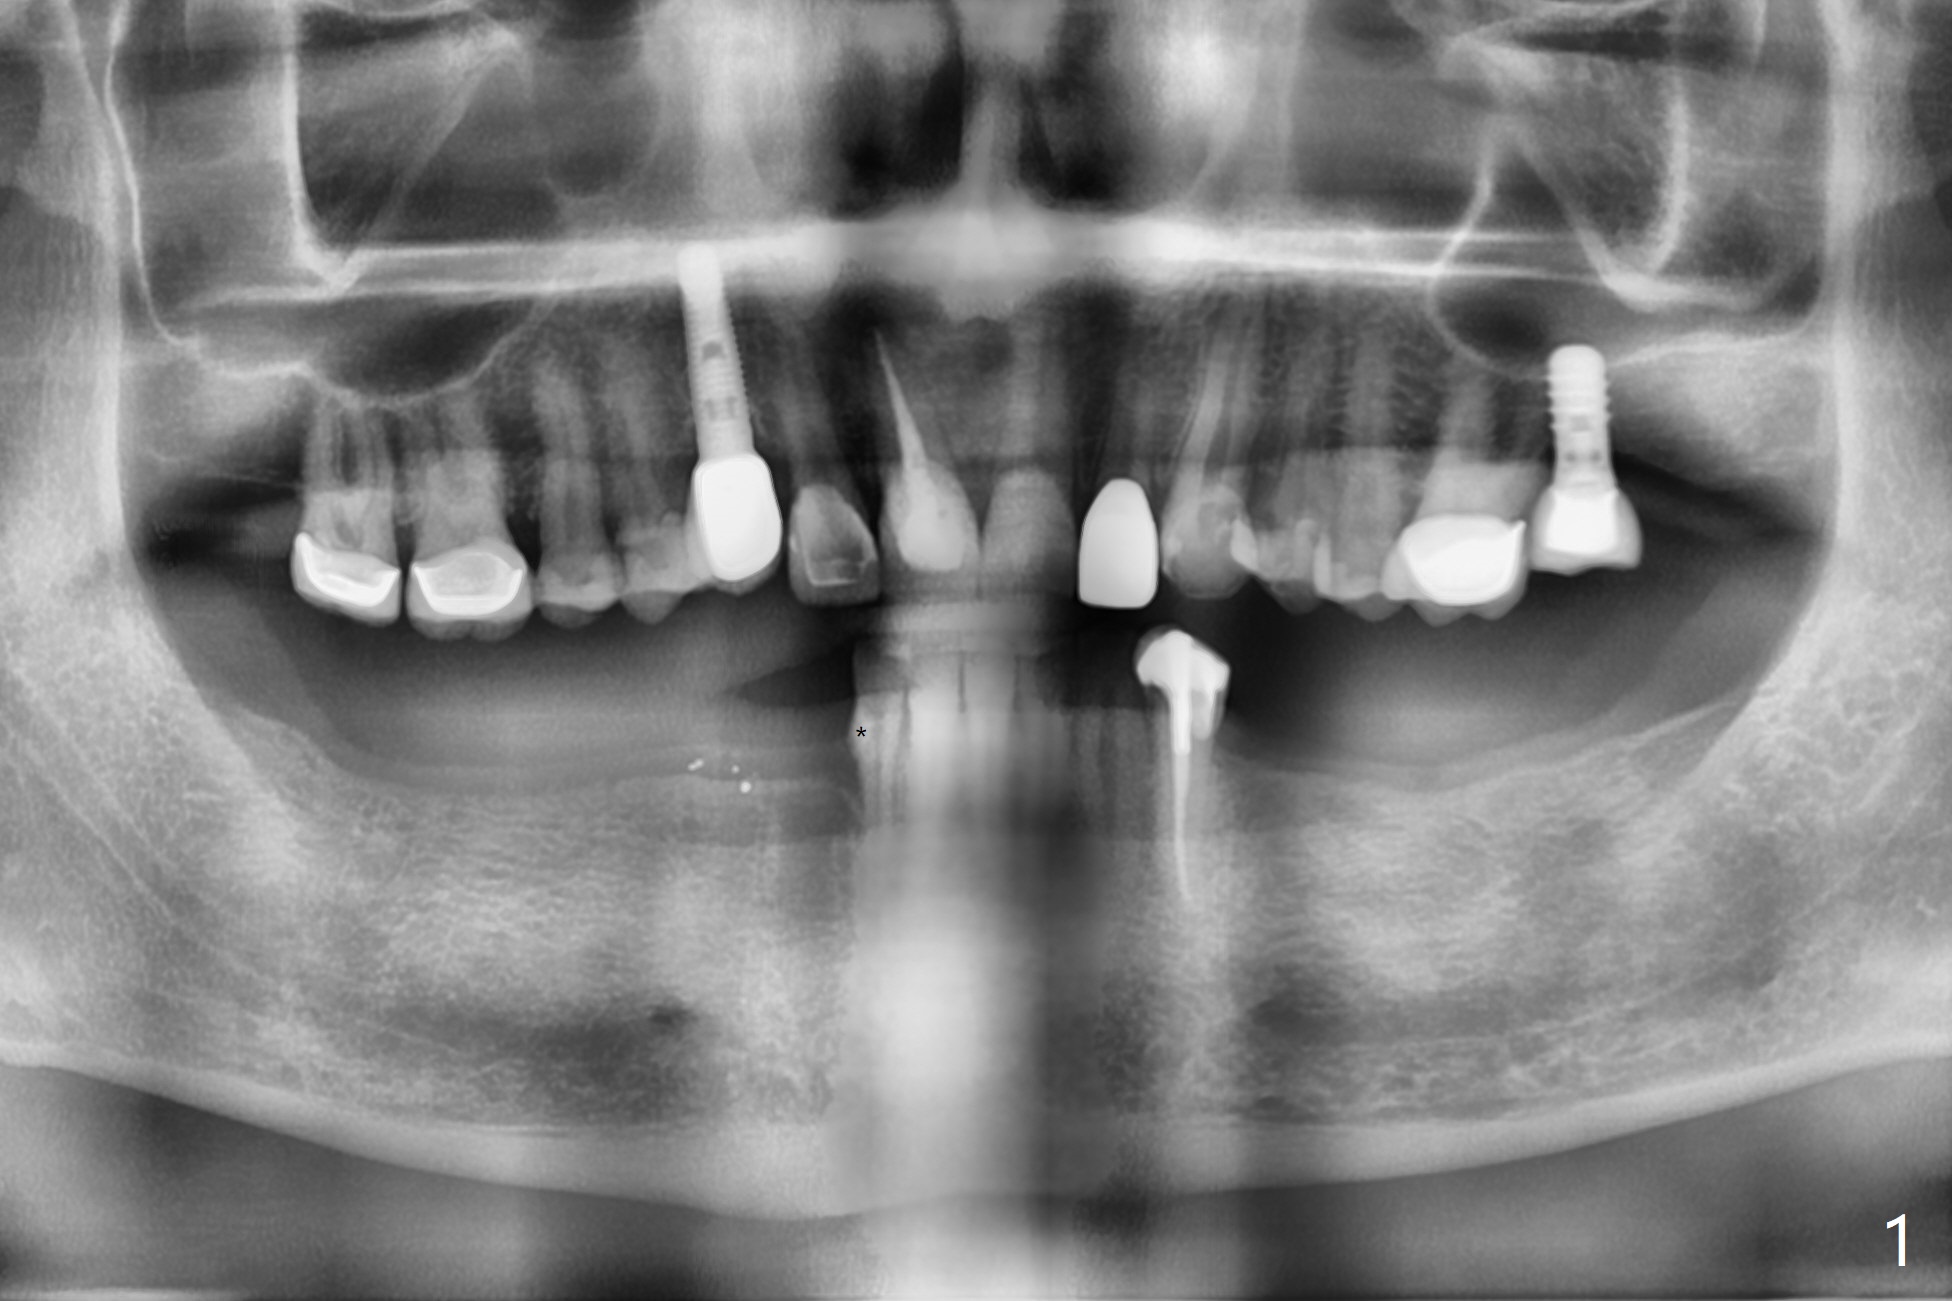

56岁男下颌可弯曲局部义齿(Valplast)靠托牙胶水固定,造成左下2远中颈部龋齿,后者修复后(图一),考虑在下7种植(图二,三),放置球帽基台固定义齿,改善口腔菌群。